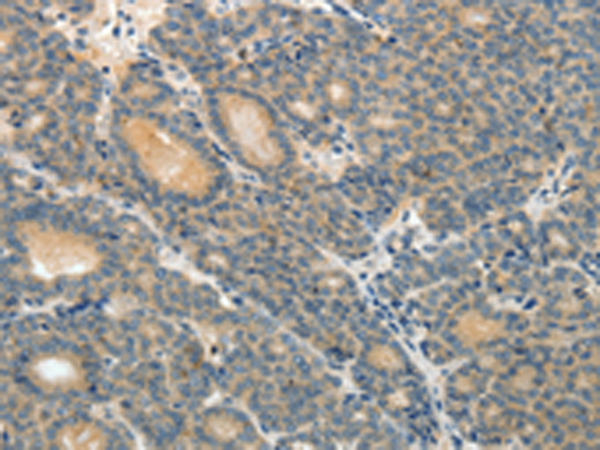

分类: 科研抗体货号: P04245别名: ALDR; ABC39; ALDL1; ALDRP; hALDR应用: IHC反应种属: Human, Mouse, Rat